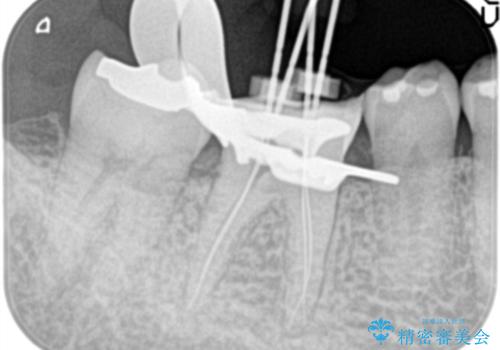

- 1週間前から冷たいもので強い持続痛を感じることを主訴に来院されました。

歯髄診断と痛みの再現により原因歯を特定し、症候性不可逆性歯髄炎の診断となりました。

根管治療〜オールセラミッククラウン(エクセレント)の治療を行なっております。